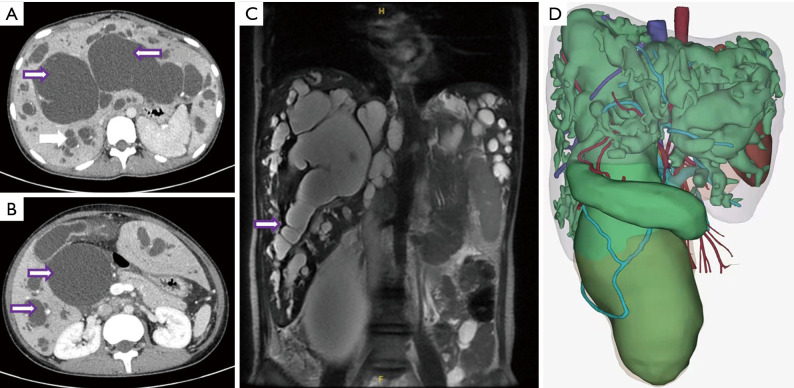

Type IVa bile duct dilatation in an adult female treated with living donor liver transplantation.